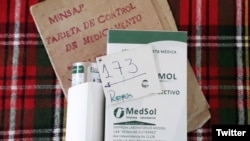

Su esposo ya había sufrido un infarto, y ahora volvió a sufrirlo por no tener el fármaco conocido por Clopidogrel, un medicamento usado para prevenir los coágulos de sangre en pacientes que han sufrido ataque cardíaco.

Tabares se encontraba en la cola de la farmacia 708 del reparto Bella Vista, en la ciudad de Camagüey desde las 4 de la madrugada para conseguir este medicamento, y otros que necesita su esposo.